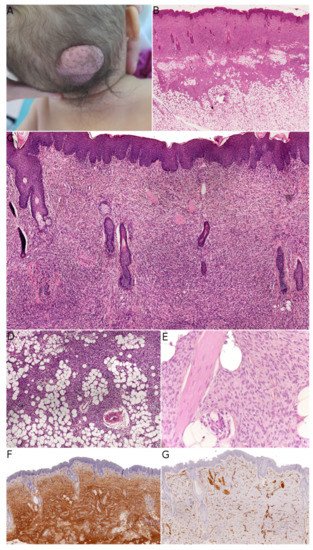

Fibroblastic connective tissue nevus (FCTN) was described in 2012 in a series of 25 cases. This variant of connective tissue nevus has some clinical and histological particularities [3][8]. It typically appears during the first decade of life as a slowly growing, painless, plaque-like, or nodular skin lesion, and is mainly located on the trunk, head, and neck and less frequently on the limbs. Girls are more often affected than boys (sex ratio: 0.5–0.6). The lesions range from 0.18 to 2.0 cm in size, and FCTN is rarely diagnosed on the basis of clinical signs alone. Histologically, FCTN is a poorly circumscribed dermal lesion that arises in the reticular dermis and extends to the superficial subcutis. In 70% of cases, there is overlying papillomatosis of the epidermis. In about 60% of cases, abnormally superficial adipocytes are seen in the reticular dermis. The tumor is composed of short, intersecting fascicles of bland, spindle-shaped fibroblasts/myofibroblasts with weakly eosinophilic cytoplasm and elongated nuclei with no atypia and no mitoses. It extends between the collagen bundles, around the appendages and into the subcutaneous septa. The most useful immunostaining marker is CD34, which is positive in 87% of cases—albeit often weakly and in focal sites. Smooth muscle actin (SMA) is weakly and focally present in less than 50% of cases, and S100 is always absent ( Figure 1 ).